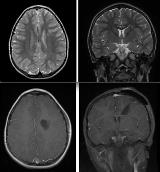

Rationale: Pediatric epilepsy patients with generalized or multifocal abnormalities on EEG and developmental delay were not classically considered for surgery, even if neuroimaging revealed a focal lesion. The new paradigm advocates for early focal epilepsy surgery, despite discordant or generalized EEG abnormalities. Current literature reflects this shift, most clearly in the realm Lennox-Gastaut syndrome symptomatic to hypothalamic hamartoma. However, this is not pervasive in current clinical practice. Many pediatric patients, especially those with developmental delay and epileptic encephalopathy, are still being overlooked for epilepsy surgery. We report here the ultimate case of focal heterotopia resection with gradual but complete resolution of seizures and behavioral abnormalities, which exemplifies that symptomatic generalized epilepsy and resultant epileptic encephalopathy may be reversible and potentially curable with resection. Methods: An eight-year-old boy began having complex partial seizures at age four, and progressed to Lennox-Gastaut syndrome with multiple seizure types, diffuse electrographic abnormalities, developmental delay, and severe behavior problems by age six. MRI revealed a left subcortical heterotopia. He was refractory to adequate trials of multiple medications and continued to have two atonic and fifteen generalized seizures daily. Despite lack of focality on EEG, the presumed cause of his intractable epilepsy was the grey matter heterotopia, and thus he underwent surgical resection. Results: Seizure frequency was improved immediately, but he still had daily seizures. He gradually became seizure free over three months and remained so even after stopping all medications with a paralleled resolution of the prior continuous generalized electrographic abnormalities. Furthermore, his behavior, learning, and speech all improved remarkably over the year following surgery. He caught up to his peers and was able to attend normal classes without special education needs. Two years after focal resection, this boy, who met criteria for Lennox-Gastaut syndrome, is normal and without seizures! Conclusions: This case exemplifies that epilepsy surgery may be successful with a focal cortical dysplasia, despite abundant generalized discharges on EEG. A focal epileptogenic process can be masked by generalized EEG abnormalities, and the generalized discordant electrical abnormalities gradually resolve after resection of the primary pathology, possibly representing secondary epileptogenesis, or at least a significant epileptic encephalopathy. Our patient demonstrates that focal resection can be curative with miraculous results, displaying the possibility for seizure freedom, resolution of epileptic encephalopathy, and return to a normal healthy childhood. This continues to reinforce early and vigorous treatment of epilepsy and the ever-expanding selection criteria for surgical candidacy. In a child with intractable epilepsy, despite discordant EEG pathology, if there is a lesion, take it out quickly!